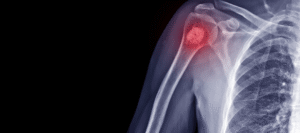

Ciudad de México.- El osteosarcoma es un tipo de cáncer óseo agresivo que suele afectar a niños y adolescentes, caracterizado...